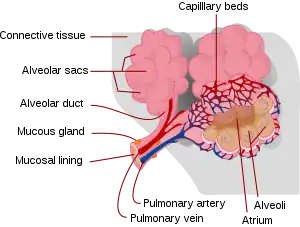

Respiratory zone

The conducting zone of the respiratory tract ends at the terminal bronchioles when they branch into the respiratory bronchioles. This marks the beginning of the terminal respiratory unit called the acinus which includes the respiratory bronchioles, the alveolar ducts, alveolar sacs, and alveoli.[27] An acinus measures up to 10 mm in diameter.[28] A primary pulmonary lobule is that part of the acinus that includes the alveolar ducts, sacs, and alveoli but does not include the respiratory bronchioles.[29]

The unit described as the secondary pulmonary lobule is the lobule most referred to as the pulmonary lobule or respiratory lobule.[25]: 489 [30] This lobule is a discrete unit that is the smallest component of the lung that can be seen without aid. The secondary pulmonary lobule is likely to be made up of between 30 and 50 primary lobules.[29] The lobule is supplied by a terminal bronchiole that branches into respiratory bronchioles. The respiratory bronchioles supply the alveoli in each acinus and is accompanied by a pulmonary artery branch. Each lobule is enclosed by an interlobular septa. Each acinus is incompletely separated by an interlobular septa.[28]

The respiratory bronchiole gives rise to the alveolar ducts that lead to the alveolar sacs, which contain two or more alveoli.[20] The walls of the alveoli are extremely thin allowing a fast rate of diffusion. The alveoli have interconnecting small air passages in their walls known as the pores of Kohn.[20]